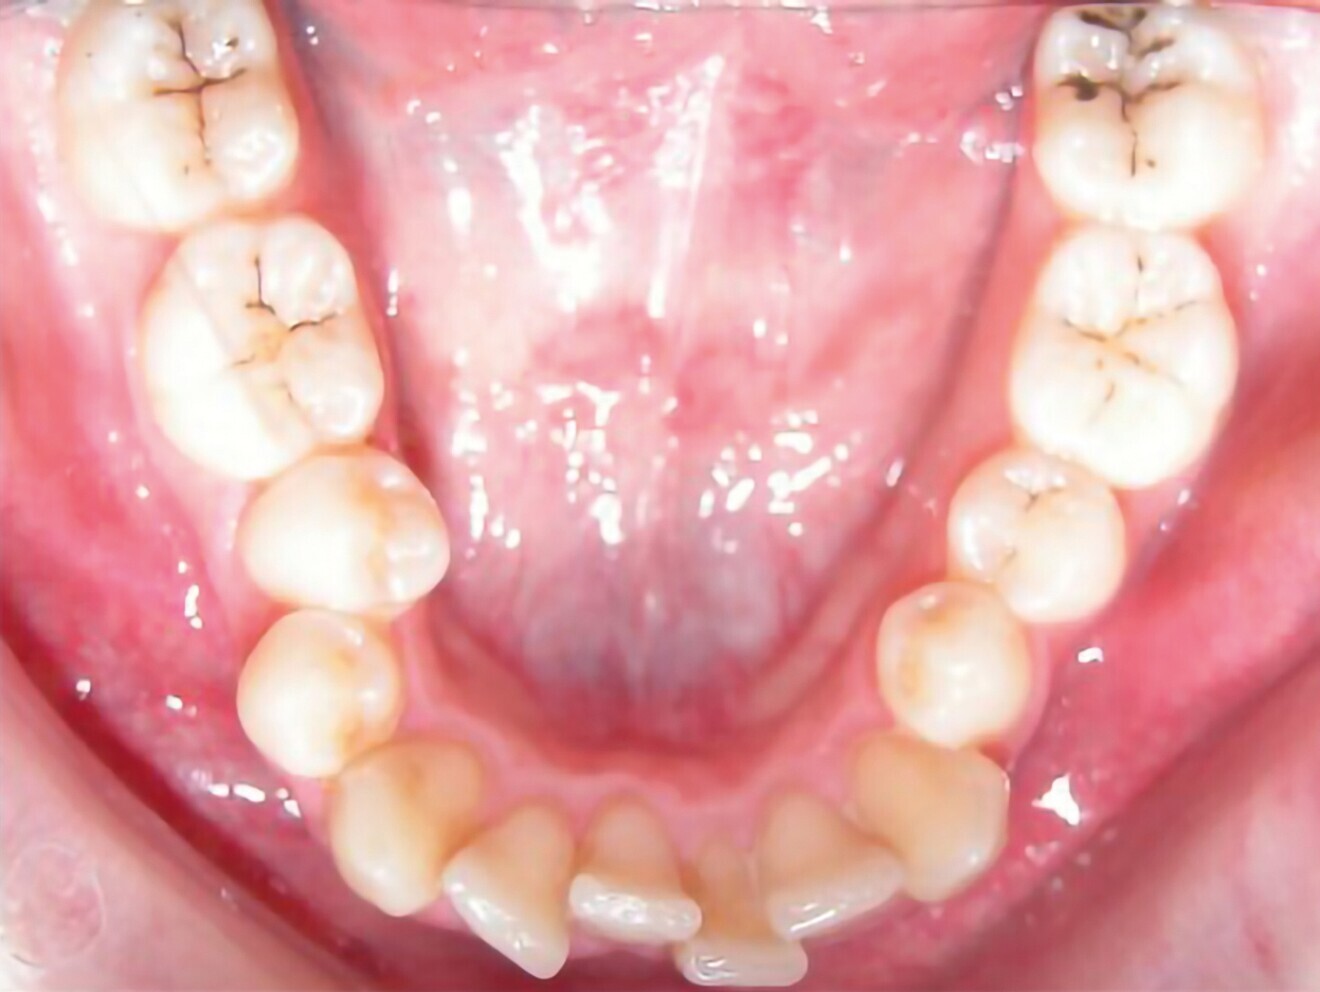

Le motif principal de consultation de la patiente, une jeune femme de 27 ans, est un encombrement dentaire accompagné d’une occlusion mal équilibrée. Danseuse de profession, elle se tracasse énormément au sujet de son apparence lors de ses apparitions publiques si elle entreprend un traitement. L’examen clinique révèle une relation d’Angle de classe I du côté droit et une relation molaire canine de classe II du côté gauche (Fig. 1).

De ce côté, les molaires, les prémolaires et la canine sont en occlusion croisée. L’examen ne montre aucun déplacement latéral fonctionnel de la mandibule. La ligne médiane maxillaire est en harmonie avec la symétrie faciale, mais la ligne médiane mandibulaire est déviée vers la gauche, en raison d’un décalage des dents de 4 mm. On observe un encombrement important des dents inférieures, évalué à 11 mm, et un encombrement modéré de 10 mm au niveau de l’arcade maxillaire. Les racines des dents 31, 33 et 43 semblent proches du rebord vestibulaire de l’os cortical, et les deux arcades présentent un rétrécissement dans la région des prémolaires et molaires.

Fig. 1b : Photographie intraorale initiale.

Fig. 1c : Photographie intraorale initiale.

Fig. 1d : Photographie intraorale initiale.

Fig. 1e : Photographie intraorale initiale.